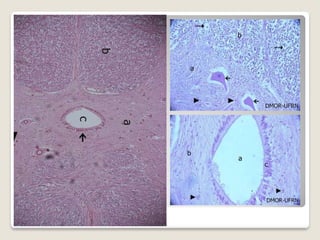

GÂNGLIOS NERVOSOS

Acúmulos de neurônios localizador fora do SNC

Células satélites: sustentação estrutural e metabólica

• 34.

GÂNGLIOS NERVOSOS Acúmulos deneurônios localizador fora do SNC Células satélites: sustentação estrutural e metabólica